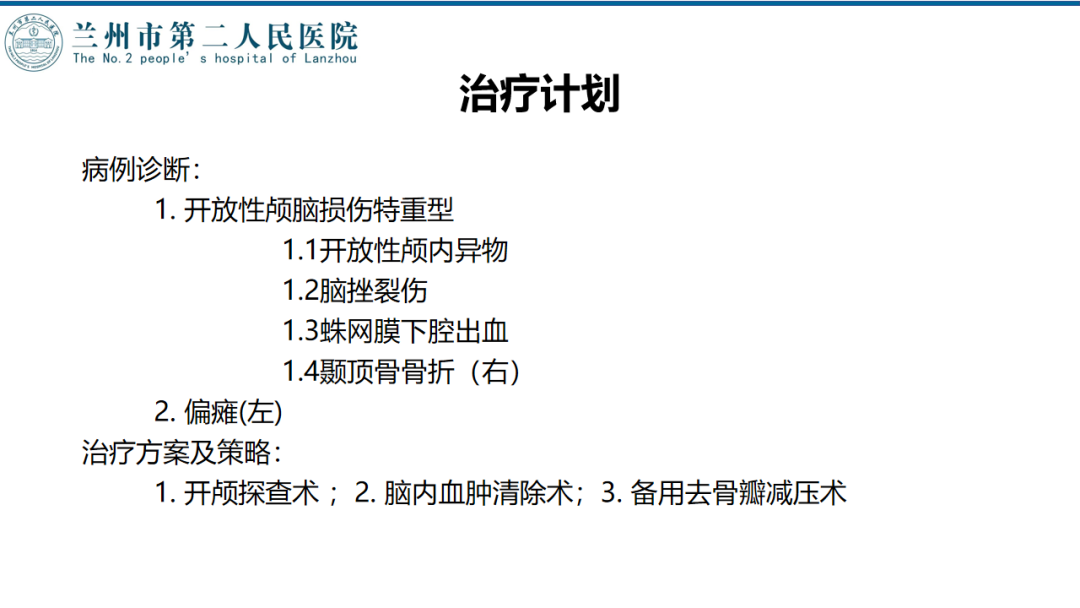

![]()

术后随访

术后CT